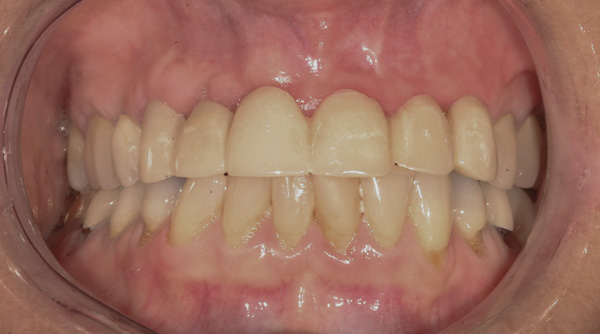

Figure 1 Patient following insertion of first set of implant custom abutments.

Figure 1